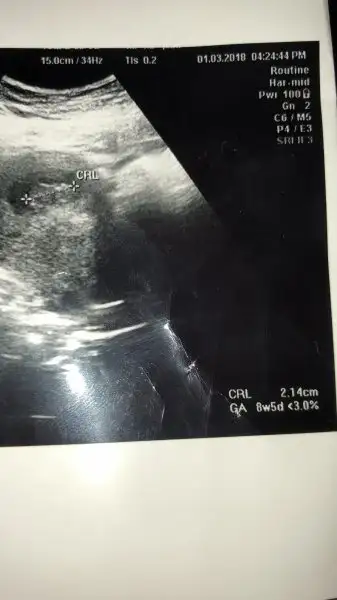

Ramzi Teorisi ve cinsiyet tahmini ( tutma olasılığı %85 miş )

• 788203CE-E874-4847-A76A-CEB2C8F3CA6C.webp

788203CE-E874-4847-A76A-CEB2C8F3CA6C.webp

13,4 KB · Görüntüleme: 173